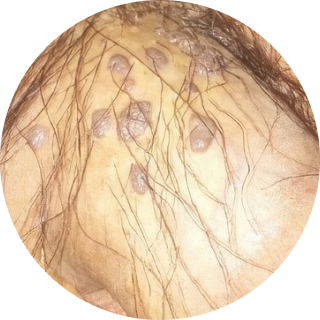

무증상인 경우도 많습니다. 여러 개가 다발로 생기고,

닭벼슬이나 양배추처럼 보기 불편한 모양을 띠기도 합니다.

양배추모양 (닭벼슬)

양배추모양 (닭벼슬) 작은 구진모양

작은 구진모양 물집 형태

물집 형태 편평사마귀

편평사마귀